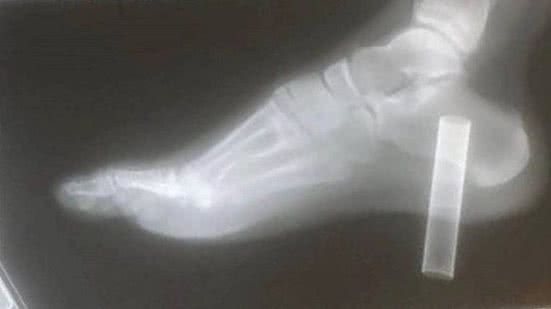

Um adolescente quase perdeu o pé direito quando um cigarro eletrônico (vape) descartável de 10cm perfurou o solado fino do seu tênis e entrou em sua carne, chegando a um osso.

Harley Bennett, de 13 anos, ouviu de um cirurgião que a amputação pudesse ser necessária devido a uma infecção em osso do calcanhar. "Eu fiquei apavorada. Eu estava com mais medo de Harley e de sua reação, vendo como ele estava com medo", disse Samantha Robinson, a mãe de Harley, de acordo co reportagem do "Sun".

Porém uma cirurgia bem-sucedida, em outubro, fez com que o risco da amputação fosse eliminado. O caso ocorreu em Cirencester (Inglaterra).

O drama começou quando Harley encontrou o cigarro eletrônico no chão e tentou esmagá-lo como se fosse uma lata de refrigerante. "Eu não estava pensando, não sei como explicar. Eu apenas pisei nele e foi direto para o meu pé. Foi muito doloroso", relatou o estudante.